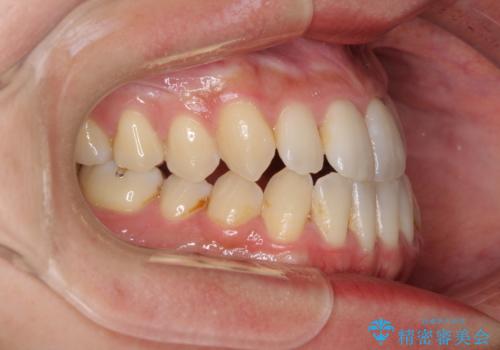

前歯のデコボコ インビザラインによる矯正治療

- 上下前歯の叢生と奥歯の反対咬合を気にして来院された患者様です。

インビザラインを用い、下顎はIPR(歯と歯の間を削る)と歯列全体を後方に移動させ、上顎は側方に拡大させることで歯列を改善していくこととしました。

骨格的に下顎が左側前方にずれているため、上下正中のズレや左右奥歯の咬み合わせを理想的な状態とすることは困難でした。